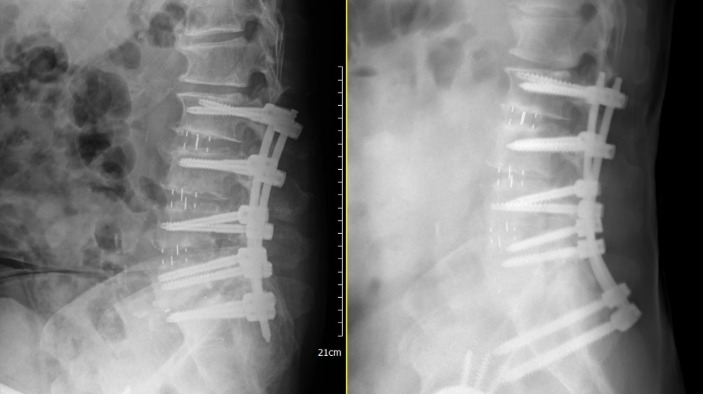

嚴重的側彎翻修常伴隨複雜的3D畸形,傳統X光已不足以提供足夠評估依據與手術導引。

通常面對複雜翻修,我們不再採用「大傷口、強行剝離」的傳統做法,而是透過3D數位電腦導航、結合多元微創路徑來進行二次翻修。

針對骨質缺損的節段,導航能協助尋找最穩固的置釘角度(如椎弓根釘的新路徑),精準度達<0.1公分。

| 比較項目 | 傳統開放式翻修 | 數位導航微創(OLIF) |

| 手術路徑 | 沿舊傷口進入(疤痕沾黏多) | 全新側方路徑(避開沾黏) |

| 失血量 | 較多,常需輸血 | 顯著減少,風險可控 |

| 神經損傷風險 | 較高(解剖構造不清) | 低(神經監測與導航雙重保障) |

| 術後復原 | 3-6 個月 | 1-3 個月 |